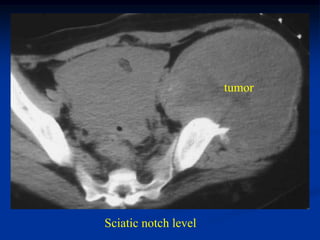

21 year female with large pelvic mass which turned out to be

a metastatic thyroid metastasis from an ovarian teratoma

tumor

Sciatic notch level

Supra acetabular level